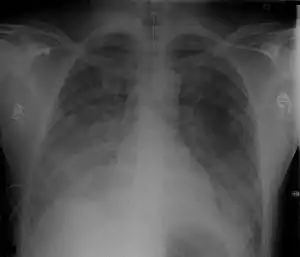

| Chest Xray of a 40 yr old male in acute respiratory distress syndrome as a complication of murine typhus | |